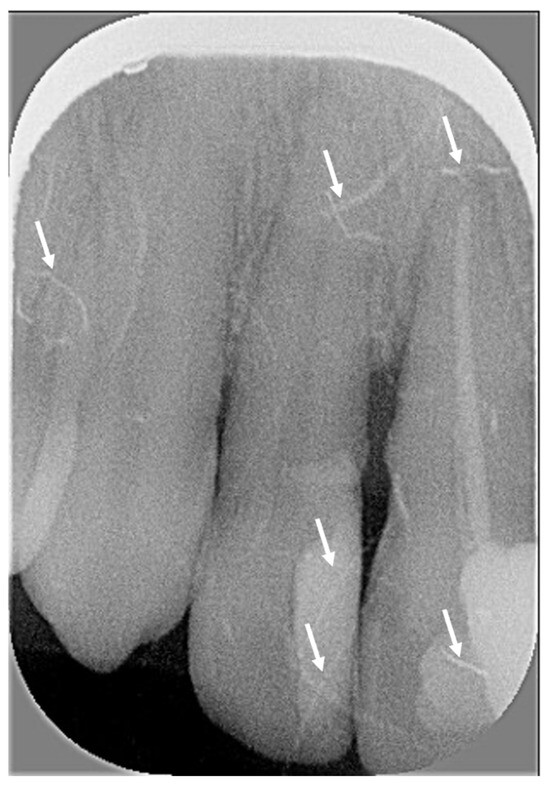

| Artefacts | Exposure to ambient light, presence of foreign object or vertical stripes | -- | No Or minimal without consequence on diagnosis | Yes With consequence on diagnosis |

| Intact digital plate, without traces of scratches, folds, or other | -- | No Or minimal without consequence on diagnosis | Yes With consequence on diagnosis | |